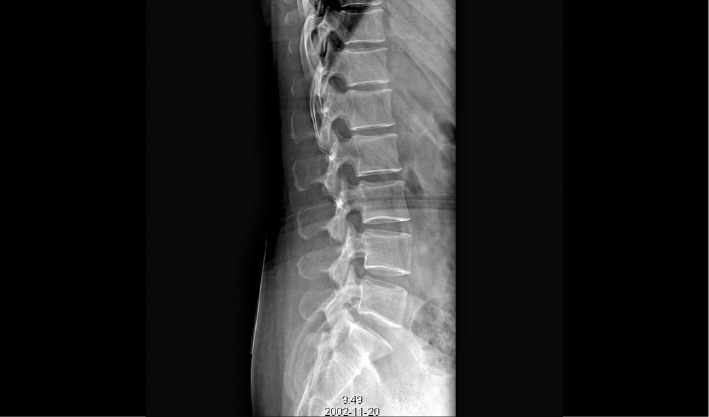

成熟优秀的动态成像技术,在透视下实时观察内部器官运动状态,并可快速高清点片,动静结合,多视角精准观察病灶。